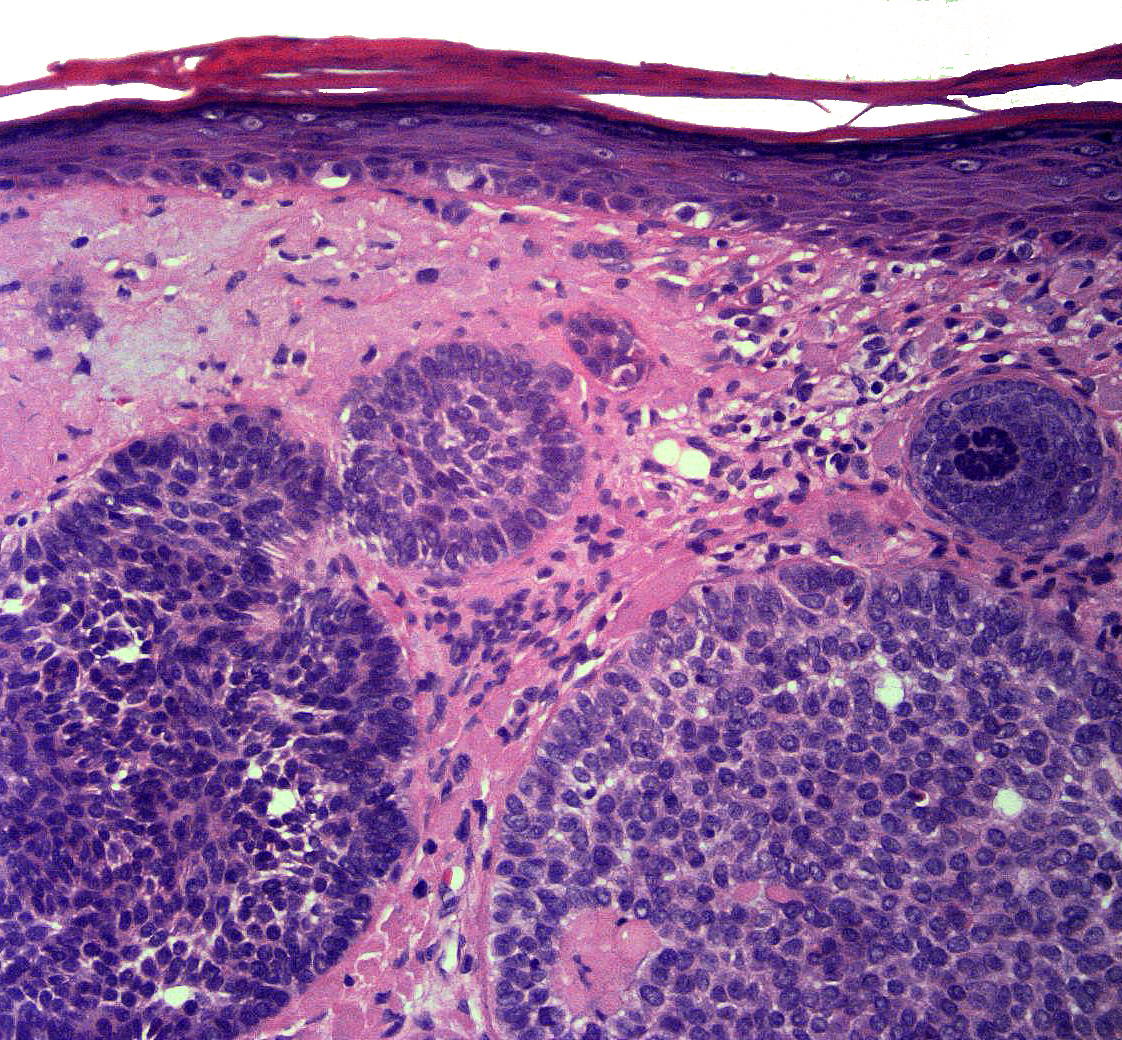

Dermatopathology

• Photomicrographs on cases available